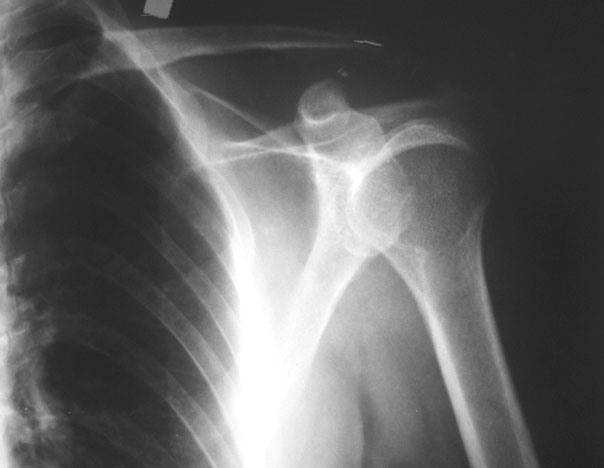

标题: X4596:左肩肿物。 [打印本页]

标题: X4596:左肩肿物。

男47,左肩疼痛月余,无红肿,无活动障碍,局部有压痛。

一般骨囊肿沿骨髓纵向生长,而本例似有横向生长趋势,建议mr或ct检查

考虑动脉瘤样骨囊肿

考虑骨巨细胞瘤,骨囊肿待排。

投照位置不好!不是正位

位置不正!可能是假影

位置不正确!可能是假影

横向膨胀,在骨端,年龄47岁,考虑骨巨细胞瘤